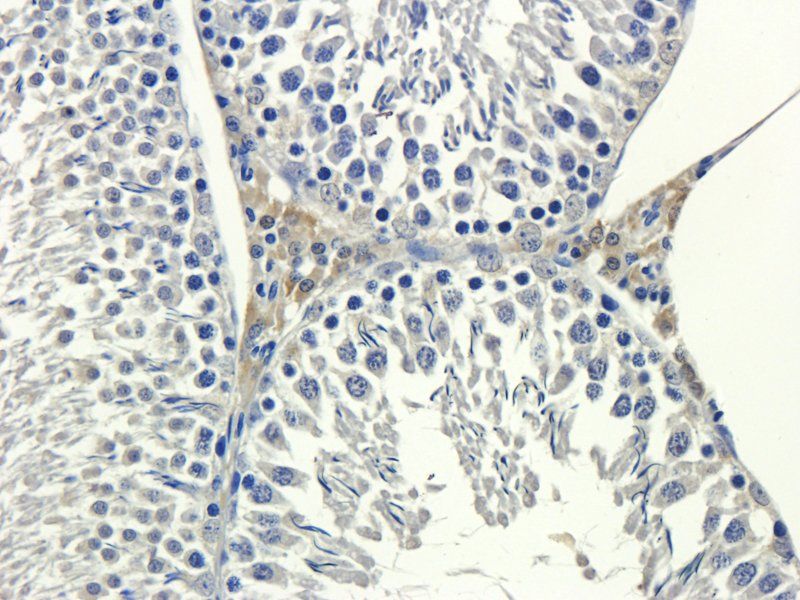

Wichtigstes Zielmolekül: E-cadherin (CDH1) Der Verlust oder die Funktionsstörung von E-Cadherin ist ein Kennzeichen der epithelial-mesenchymalen Transition (EMT), einem Prozess, der für die Metastasierung von Krebs entscheidend ist, da er die Ablösung und Invasion von Tumorzellen erleichtert. Die Untersuchung des E-Cadherin-Status mittels Antikörpern in der Immunhistochemie (IHC) oder durch ELISA-Quantifizierung ist nach wie vor von grundlegender Bedeutung für die Krebsdiagnostik und -forschung.

E Cadherin 1/CDH1 Antikörper |